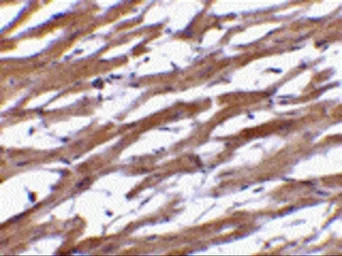

IHC-P analysis of human heart tissue using GTX85073 BAP29 antibody.

Working concentration : 20 μg/ml